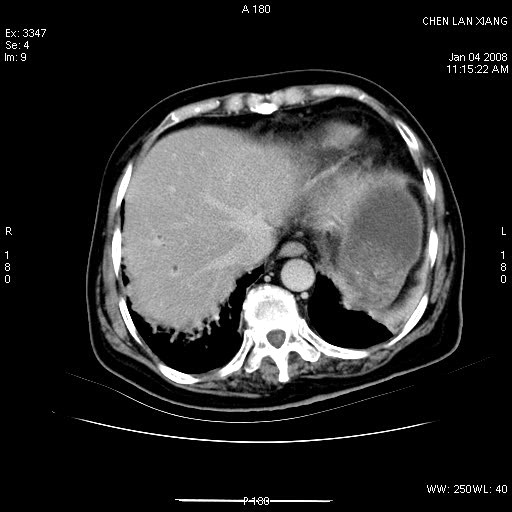

标题: CT11180:女,76岁,腹痛3-4天 [打印本页]

女,76岁,腹痛3-4天,b超示:肝内实性肿物,胆囊强回声,胆总管扩张.

考虑:1、胆总管下端结石伴梗阻性肝内外胆管扩张(肝左叶外侧段肝内胆管多发结石、胆管炎);

2、肿囊癌累及肝,不除外 黄色肉芽肿性胆囊炎。

1 胆总管末端结石伴肝内胆管结石,肝内外胆管扩张。2 胆囊扩大,胆囊壁不规则增厚,内见软组织密度影。考虑:慢性胆囊炎,不除外胆囊癌!

胆总管末端结石伴肝内胆管结石,肝内外胆管扩张。低位胆道梗阻2 胆囊扩大,胆囊壁不规则增厚,内见软组织密度影。考虑:慢性胆囊炎,不除外胆囊癌!

胆囊密度增高,增强后周边肝组织及胆囊窝下部周边软组织延时性不规则强化.然胆囊壁未见明显不规则增厚及肿块.左侧肝内胆管及胆总管下段结石伴胆系扩张.

考虑;胆囊炎(黄色肉芽肿性胆囊炎?),左侧肝内胆管及胆总管下段结石.

ct所见:1、 肝内胆管结石,肝内外胆管扩张。低位胆道梗阻,胆总管下端结石;2 胆囊扩大,胆囊壁不规则增厚

考虑:胆总管下端结石并肝内外胆管扩张,肝内胆管结石;

标题: 肝右叶病灶

胆囊癌侵犯肝右叶?

1)胆囊癌伴肝脏转移。2)胆总管下端结石、肝内胆管结石伴肝内外胆管扩张。